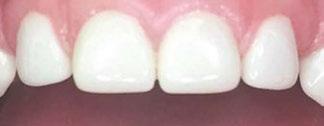

Several clinical solutions exist for primary anterior teeth with multisurface decay. Full coronal restoration of carious primary incisors may be indicated when caries is present on multiple surfaces, pulpal therapy is indicated, caries may be minor, but oral hygiene is very poor, or in a child with severe early childhood caries or a high caries risk diagnosis.1 Depending on the clinical scenario, a minimally invasive approach with the utilization of a high viscosity glass ionomer cement (HVGIC), with or without the combination of silver diamine fluoride (SDF) in a strip crown form, may pause the caries progression and provide an adequate clinical solution. Resin composite strip crowns have shown 80% retention rates and adequate parental satisfaction,1-4 although composite resin strip crowns have shown lower retention rates in teeth with decay involving three or more surfaces and particularly in children with a high caries risk4-6 (Figure 1). This could be from the continued high caries risk behaviors of the patient, as composite resin strip crowns in this population have shown to have increased inflamed marginal gingiva and gingival bleeding, increased plaque retention along the restoration, and loss of some restorative material.5,6

Alternatively, a resin-faced stainless steel crown provides a full coverage restoration with excellent retention.7 These crowns can serve as a full-coverage restoration with or without the resin facing, but the loss of resin facing can be a major esthetic concern for parents.7 Preformed pediatric zirconia crowns address many of the undesirable clinical outcomes of other restorative materials. Their biocompatibility, demonstration of excellent marginal gingival health, low plaque retention, high parental esthetic acceptance, and high survival probabilities make them an excellent clinical choice in the patient with severe early childhood caries.1,4,5,8-13

With parental interest increasing in esthetic treatment options for complex anterior caries, preformed pediatric zirconia crowns are becoming the treatment of choice for patients with a high caries risk or a severe early childhood caries diagnosis.14

2: NuSmile® Anterior Zirconia crowns at 2-year follow up. Note the high amount of plaque accumulations along the untreated cuspid and existing stainless-steel crowns

This review discusses three clinical cases in which NuSmile® ZR (NuSmile, Houston, Texas) anterior pediatric zirconia crowns were the correct clinical decision in varying clinical scenarios.

Figure 1: Occlusal films at recall visit in high caries risk patients showing loss of material and recurrent decay in composite resin strip crowns Figure